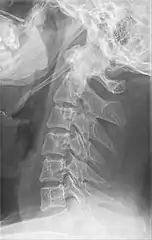

| Anteroposterior and lateral radiographs of cervical spine showing ossification of the stylohyoid ligament on both sides | |